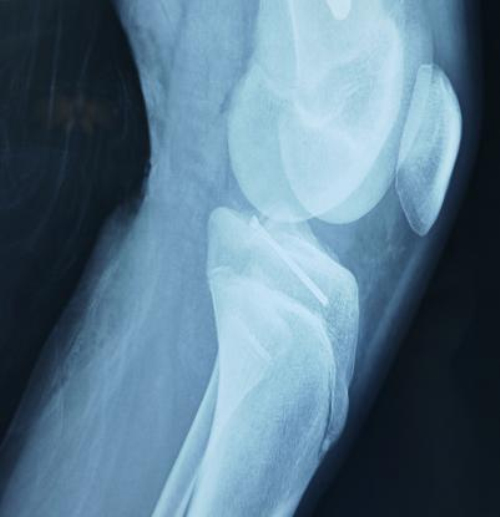

患儿因车祸导致左胫骨髁间后棘骨折,骨折移位明显, 具备手术指征。考虑到儿童骨折的特殊性,除了要考虑骨折 复位满意、固定牢靠之外,还需要考虑手术方式是否影响患儿的生长,同时也要考虑手术疤痕影响皮肤美观。因传统手术方式无法满足患者需求,且创伤大、恢复慢、美观性差,并可能因切开复位损伤患儿股骨近端生长板而导致出现新的畸形。

术前核磁光片